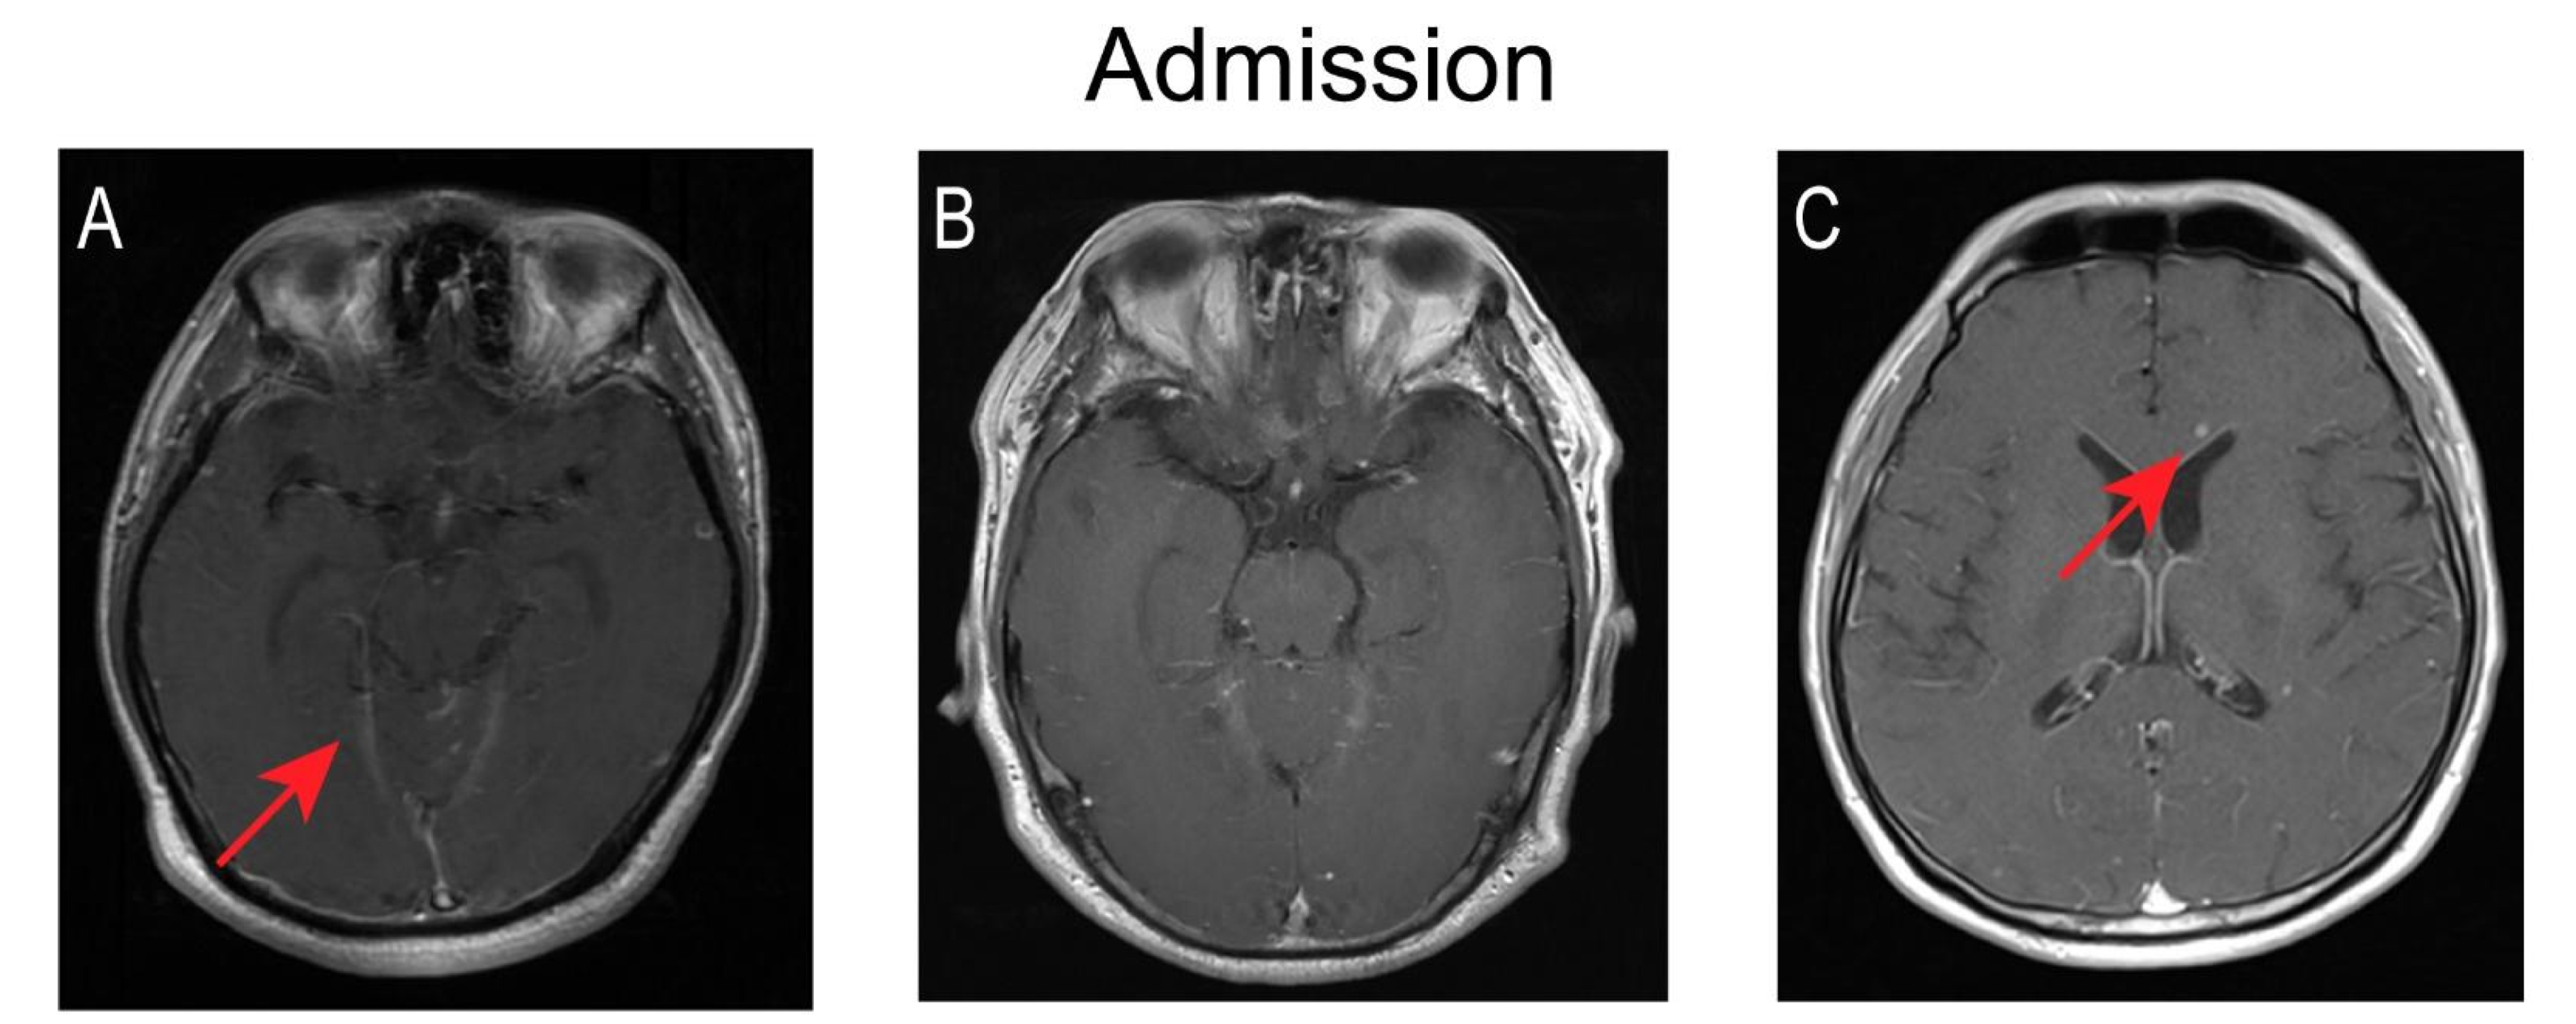

Figure 2.

Changes of brain MRI before and after anti-tuberculosis treatment. The MRI sequence is Gd-enhanced MRI T1 cross-sectional; (A–C) The images of cases 1, 2, and 4 at admission. (A) Significant enhancement of pontine cistern as well as cerebellar vermis cistern. (B) No abnormal findings. (C) Scattered nodules of varying sizes in the brain parenchyma. (D–F) The images of cases 1, 2, and 4 after treatment for one month. (D) New nodular enhancement lesions were seen in the medulla oblongata in one patient. (E) Multiple new nodular enhancement lesions can be seen in the left frontal lobe of another case. (F) The lesions in the lateral ventricular angle were larger and more intense. (G–I) The images of cases 1, 2, and 3 after treatment for eight, three, and six months respectively. Follow-up imaging upon treatment showed resolution. (G) The lesions in the medulla oblongata of case 1. (H) The lesions in the left frontal lobe of case 2. (I) The lesions in the lateral ventricular angle of case 4.

During the course of HRZE treatment, the patients underwent lumbar puncture and brain MRI imaging at various time points to monitor any changes in condition and treatment response. The dynamic changes in various CSF indices in the five patients are shown in Figure 1. Three of the five patients showed a fluctuating downtrend in the white cell count during the first month of antibiotic treatment. Lymphocytes remained the predominant white cell type throughout the course of treatment in all five patients. At the last lumbar puncture, the CSF indicators returned to the normal range after treatment. Nonetheless, imaging findings deteriorated in four of the five patients during the first treatment month. In particular, the numbers and size of intracranial lesions in three patients grew for a time but had shrunk or disappeared at the last brain MRI examination. One patient had three brain MRI examinations within one month of symptom onset, which revealed worsening bilateral (but predominantly left side) meningeal enhancement in conjunction with frontal lobe edema. Five patients had enhancement of leptomeninges, and one patient had significant enhancement of the pontine cistern as well the cerebellar vermis cistern. There were no findings of hydrocephalus in four patients during the sequential imaging examination. Figure 2 presents the imaging results of three patients before and after treatment.

Within one month of anti-tuberculosis treatment, the symptoms of five of our patients had improved, even though the imaging manifestations had deteriorated in three patients, a phenomenon known as a paradoxical reaction [24]. Recent studies have shown that the paradoxical reaction may be a normal manifestation of anti-tuberculosis treatment, and has nothing to do with the prognosis and morbidity [25]. We note that the deterioration of imaging is more like a delayed manifestation of the disease. Regarding neurological signs, one of our patients had an intractable hiccup and another had mild cognitive impairment at the time of admission; culprit lesions of the medulla oblongata and left frontal lobe respectively appeared on a head MRI one month later. Overall, hydrocephalus is the most common complication of TBM, occurring in 40% of cases according to the largest follow-up study conducted by Mohammad Wasay [25], but this was not a finding in our cases.